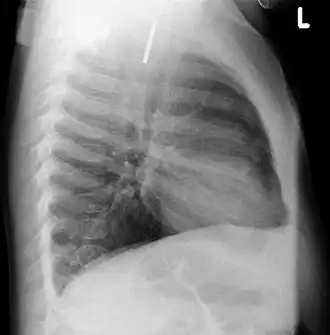

A coin seen on lateral CXR in the esophagus -